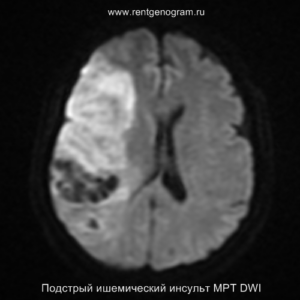

На МРТ и КТ изменения могут отсутствовать. На МРТ у некоторых пациентов могут быть первые признаки ишемии. На DWI область ишемического повреждения может быть видна через 2,5 часа после появления первых симптомов.

С 4-5 часов на DWI должны быть заметны признаки ишемического поражения, которые представляют собой «ядро» инфаркта.

Острая фаза (6 — 24 часа)

В течение острого этапа на МРТ и КТ выявляются все морфологические признаки ишемического инсульта. Область острого ишемического инфаркта визуализируется как зона ↑Т2, ↑Flair, ↑DWI и ↓Т1 ↓ADC. Можно обнаружить тромб в артерии. На КТ в остром этапе также чётко дифференцируется поражённая область, представляющая собой участок с потерей дифференциации мозговых структур и снижением их плотности. Контрастирование в остром периоде не показывает патологических участков с накоплением контраста.

Подострая фаза (24 часа — 6 недель)

На подостром этапе происходит разрушение гематоэнцефалического барьера, что приводит к вазогенному отеку, увеличивая объем ишемического инфаркта, возникновение масс-эффекта и возможного вклинения в случае обширного поражения (например, вклинение поясной извилины под фалькс или миндалин мозжечка в большое затылочное отверстие).

Разрушение гематоэнцефалического барьера (ГЭБ) приводит к накоплению контрастного вещества в области ишемического инсульта, используя технику контрастирования по «гиральному типу».

Когда в мозговых артериях происходит реканализация кровотока, это может привести к образованию геморрагических пропитываний и кровоизлияний («красный компонент» ишемического инфаркта), что будет отображаться на МРТ как ↑ на Т1 и Т2*, а на КТ — как участки с гетерогенной повышенной плотностью. На более поздних этапах подострой стадии наблюдается нормализация ранее повышенных показателей DWI и ADC, известная как «псевдонормализация» диффузии.